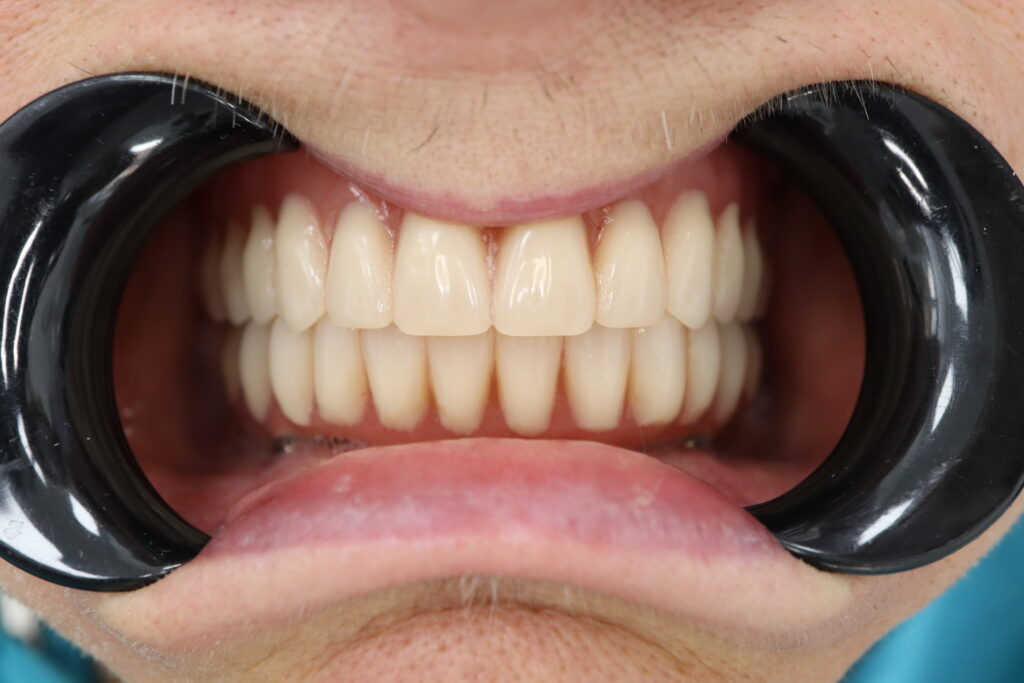

Спустя 7 дней на нижней челюсти зафиксирован металлоакриловый протез из 12 зубов с опорой на 4 дентальных имплантата.

На верхнюю челюсть изготовлен съемный акриловый протез.

Результаты

результат